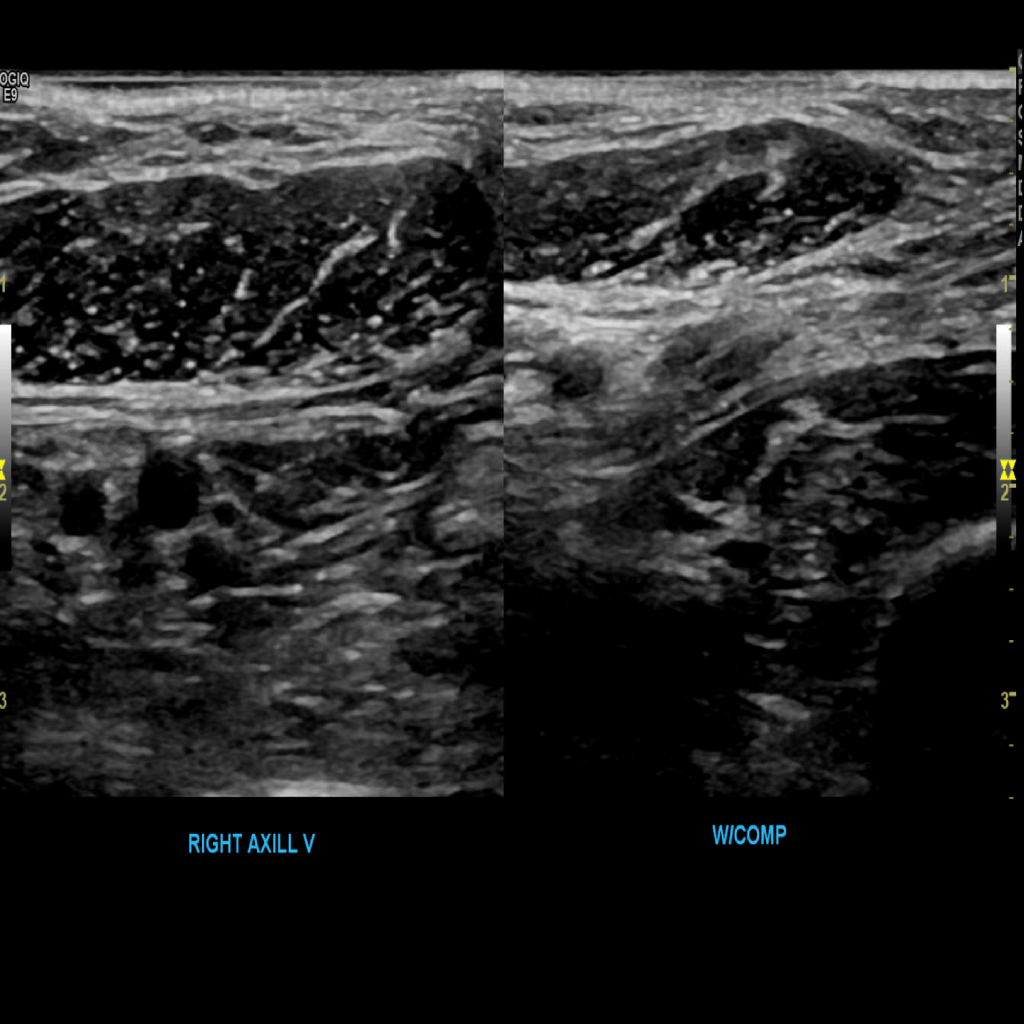

Scan the axillary vein in grey scale, compression, color doppler and spectral doppler